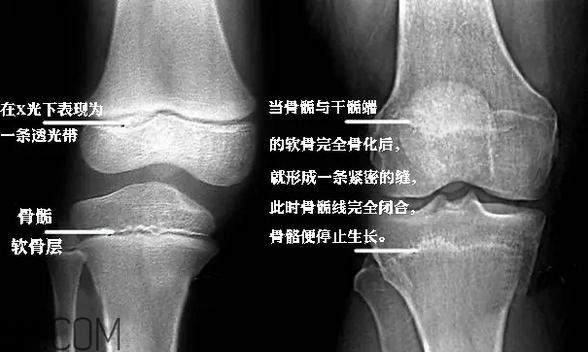

“骨骺”是儿童出生后在不同时间内出现的二次骨化中心,通俗一点就是骨骼的生长点。

适量的运动会刺激生长点,促进孩子的生长发育。

但是运动量过大时,就会造成慢性疲劳,损伤到骨骺,就会影响到孩子的生长发育了。

所以,只要是适当的年龄,寻找专业的工作室和培训机构,根据孩子的年龄适当地进行练习,对孩子的身体是完全有益的。